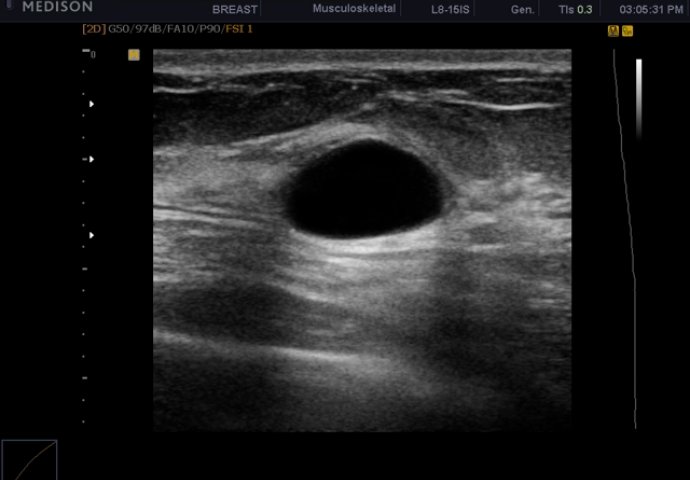

Ciste su okruglog oblika, pokreću se pod pristima i relativno su čvrste - nisu tvrde "kao kamen". Moguće je da se pojavi samo jedna, kao i da bude više njih u dojci. U prosjeku, oko 25 odsto svih kvržica u dojkama budu ciste, benigne promjene, a neke uopšte i ne izazivaju bol.

Najčešće se javljaju kod žena u četrdesetim godinama i ne zahtevaju nikakvu terapiju. Konačna dijagnoza može se postaviti ultrazvučnim pregledom. Ako je jednostavna, ali veća od 12 do 15 mm ili je složena i daje simptome u vidu bola, ljekar obavlja aspiraciju tečnosti iz ciste iglom. Izvađena tečnost ide na laboratorjski, citološki prebled. Ukoliko je tečnost krvava, smeđa ili mutna i ukoliko se ponovo pojavi nakon pražnjenja nakon 12 nedelja, hirurški se odstranjuje budući da je, rijetko, moguć razvoj raka dojke.